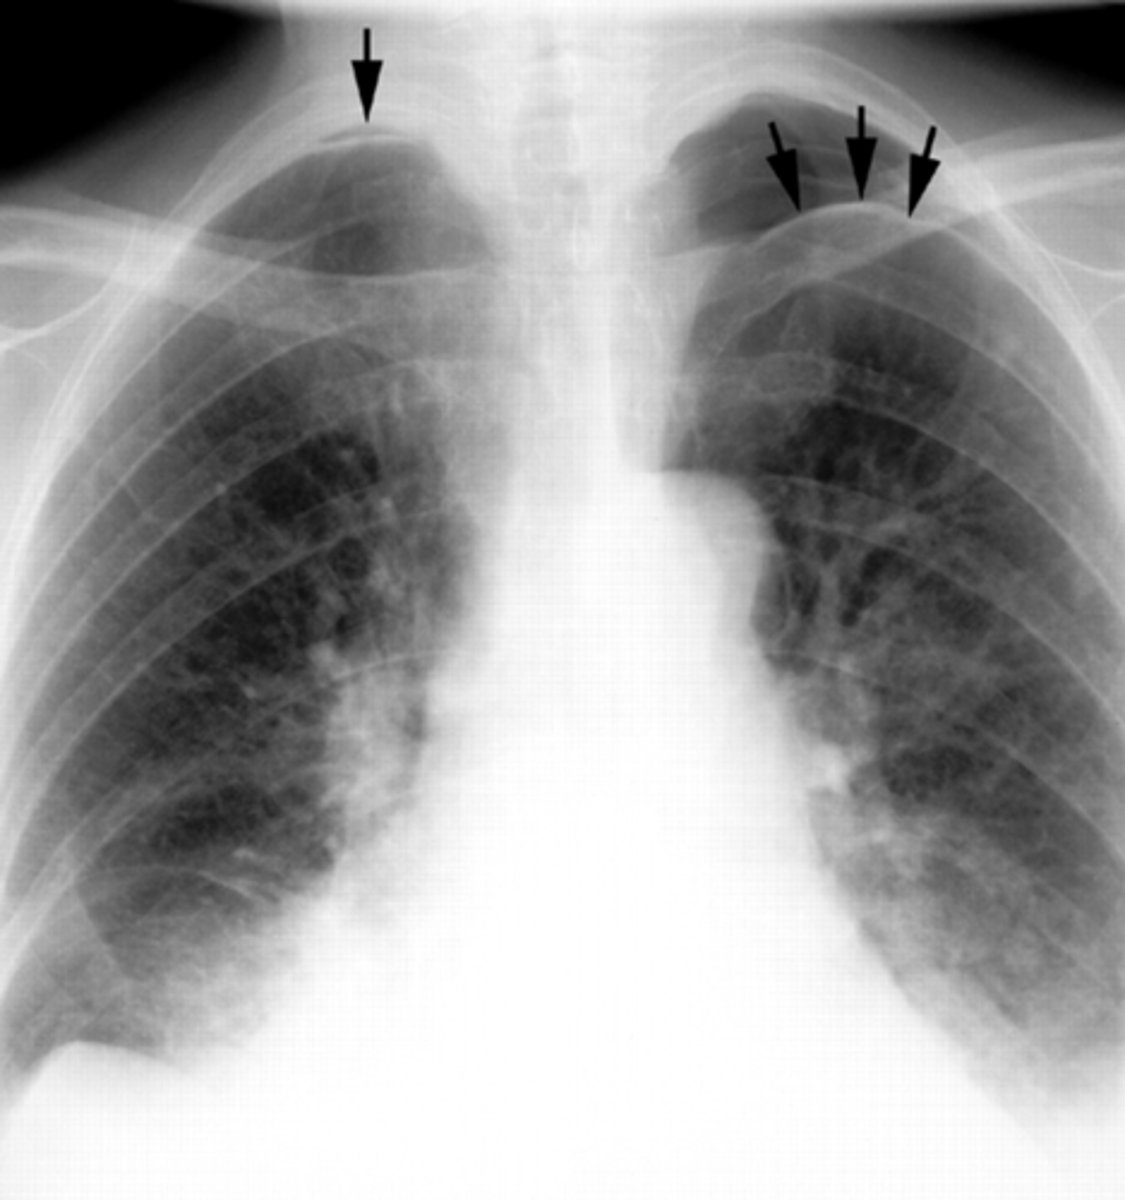

Bronchiectasis

knowt flashcard image

Tram track lines